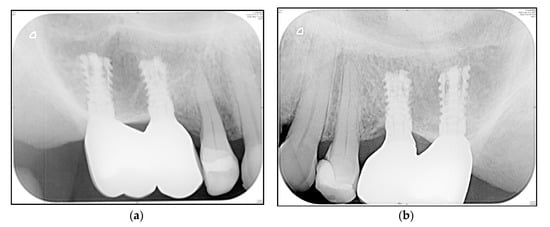

3.4. Crestal Bone Changes